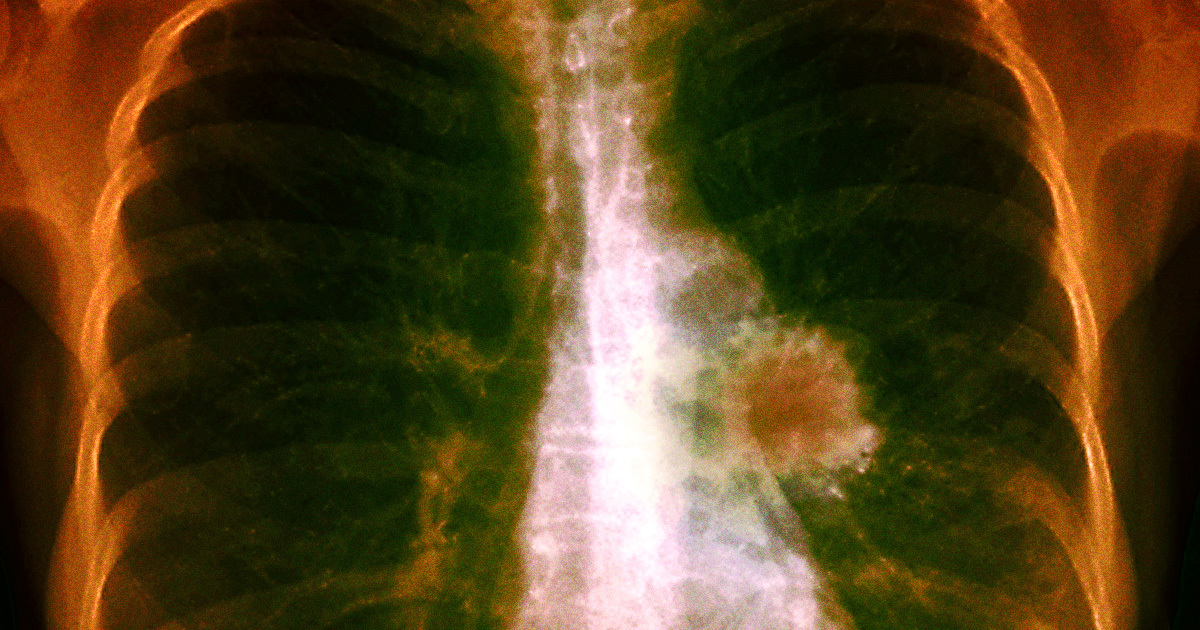

In a development that scientists have reportedly called “thrilling” and “unprecedented,” a decade-long global study has shown that a once-daily pill reduces the risk of dying from lung cancer by over half.

Taken after tumor-removal surgery, the drug, known as osimertinib, was shown in the study — published Monday in The New England Journal of Medicine — to lessen the risk of patient death by 51 percent worldwide. As it probably goes without saying, that’s a huge deal — and researchers certainly aren’t taking it lightly.

To study the potential impacts of the drug, researchers enrolled roughly 682 non-small cell lung cancer patients — non-small cell cancer being the most common form of the lung disease — from 26 countries worldwide, all aged between 30 and 86 years old. Of those hundreds of patients, 339 randomly received the AstraZeneca-made osimertinib pill, while 343 were given a placebo.

Ultimately, study results revealed that after five years, the non-placebo group observed a survival rate of 88 percent. That’s a resounding success compared to the placebo group, which saw a markedly lower survival rate of 78 percent.